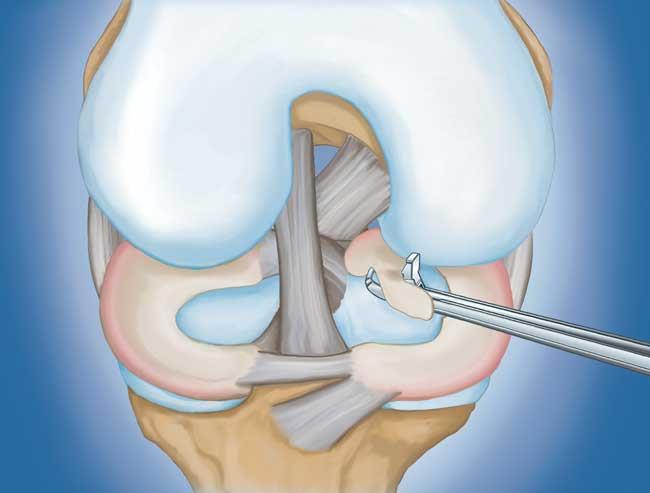

- 部分半月板切除術(shù)。 在這個(gè)過程中,受損的半月板組織被修剪掉。該程序通常允許在手術(shù)后立即負(fù)重和全方位運(yùn)動。

在這段簡短的手術(shù)視頻中,半月板部分切除術(shù)期間使用電動剃須刀平滑了退行性半月板撕裂。